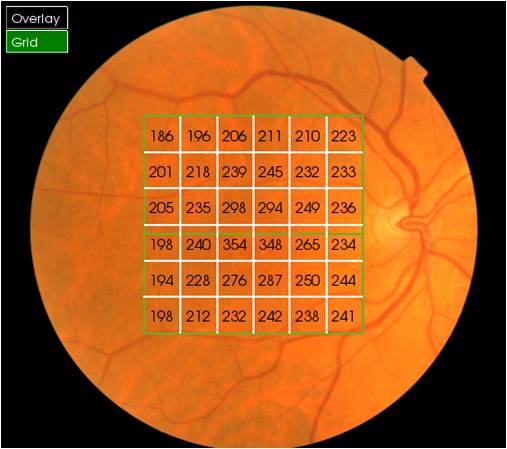

Optical Coherence Tomography (OCT) is an advanced eye scan, similar to ultrasound. The OCT uses light rather than sound waves to illustrate the different layers that make up the back of the eye. Within 2 seconds, the OCT takes over 30,000 individual scans of the back of the eye and this is used to produce a 3D image of the retina and optic nerve. The scan gives an accurate cross-sectional map through the retina and allows examination of the back of the eye in incredibly fine detail.

The OCT also captures a digital photograph of the surface of the eye at the same time, and this can then be cross-referenced with any areas of concern.

An OCT scan will allow us to detect and monitor any changes to your eye health much earlier than other methods of screening your eyes. The early detection of eye conditions such as glaucoma allows treatment to be offered long before any symptoms are noted.

The scan shows us beneath the surface of your retina, so we can see and better understand the very fine changes which can be indications of something unhealthy or abnormal.

With all your scans stored with your records, we are able to easily compare the OCT images from test to test and can quickly pinpoint any changes to the health of your eyes.